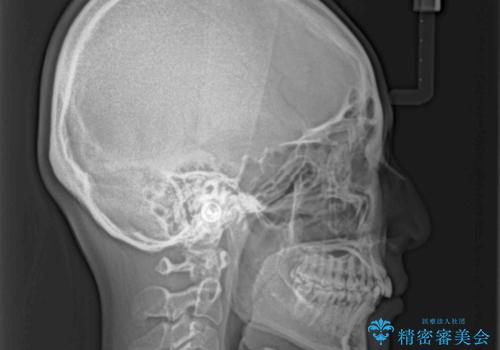

奥歯の噛み合わせをみると、上顎歯列が全体的に前突している状態であり、この咬み合わせのまま歯列を整えると出っ歯になってしまう可能性がありました。

アンカースクリューと補助装置を使用して上顎大臼歯を遠心移動させることで咬み合わせを改善し、ワイヤー装置によりデコボコを解消しながら口元の突出感も改善していくこととしました。